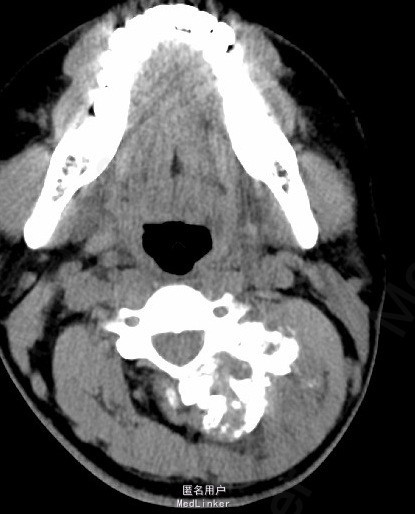

辅助检查:颈椎正侧位片示:颈部左后份软组织内见多发片状稍高密度影,约C2、3椎体平面,与椎体附件结构分界不清,颈部MRI检查示:左颈后肌间隙肿块,大小约4.9*3.9*5.4cm,考虑肿瘤病变可能性大,其他待排。入院后积极完善相关检查,查CT示:约颈3-4平面左侧软组织内见类圆形混杂密度肿块影,最大截面约4.6x4.5 cm,内见多发不规则钙化灶,增强扫描见不均匀强化,局部与邻近附件骨质关系密切,局部皮质稍显毛糙,上述考虑肿瘤性病变可能